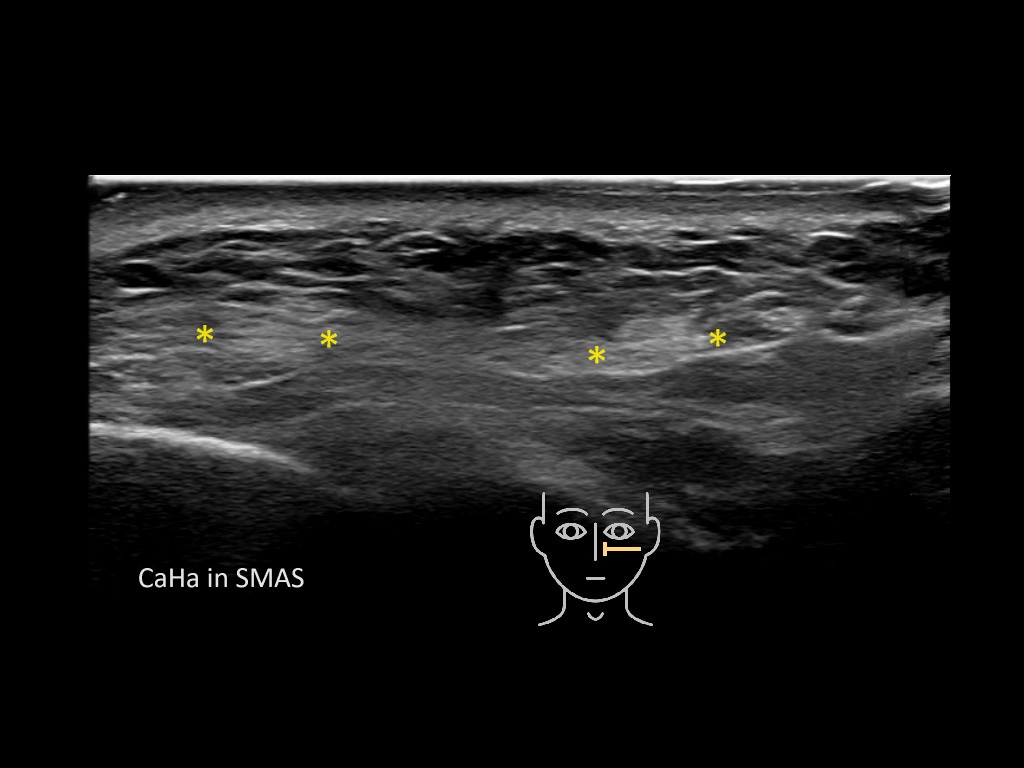

Filler deposits may end up unintentionally in the SMAS or fascial layers of the skin. Very often this will not lead to adverse events, however, adverse events ( nodules, migration / redistribution impaired muscle movement and smiling and malar edema) are are often related to filler ending up in the SMAS or fascia.

Study the first image to recognize the different layers. If you are sure about the layers, swipe to the second image to view the answer (if applicable).